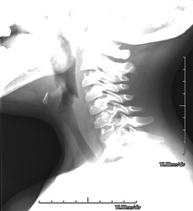

Técnica mediante la cual, utilizando rayos X, se obtienen imágenes del cavum para su estudio. Indicaciones: dificultad respiratoria, anginas de repetición en lactantes y niños. - RX Columna cervical

Técnica mediante la cual, utilizando rayos X, se obtienen imágenes de la columna cervical para su estudio. Indicaciones: traumatismo, contractura cervical, dolor articular. - RX Huesos propios nasales

- Cervical spine X-ray

This technique uses X-ray rendered imaging for examining the cervical spine. Indicated for: trauma, cervical pain.